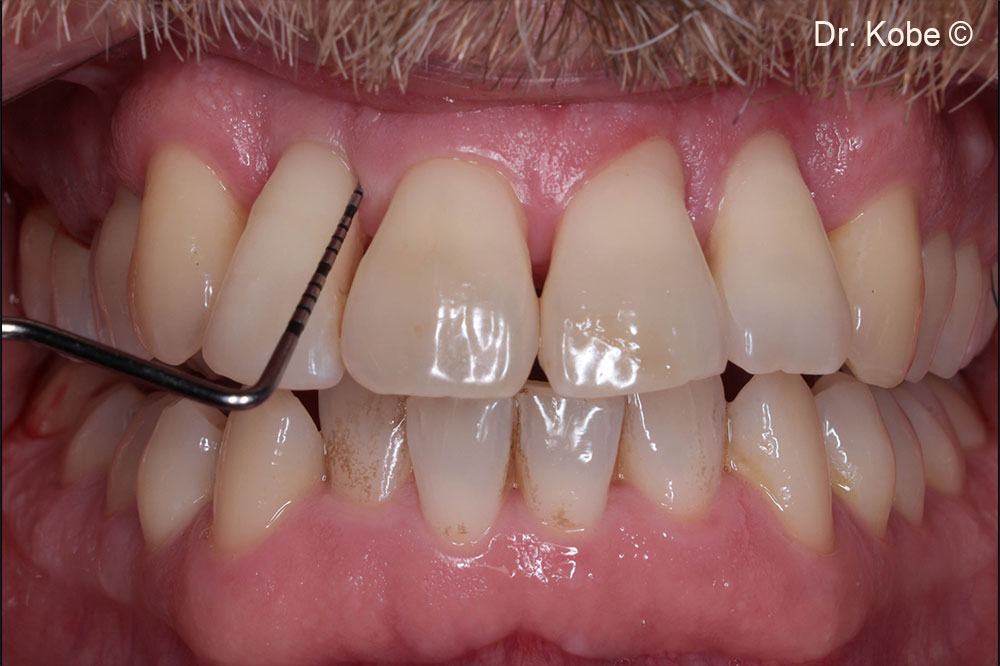

Initial situation

A male patient (40 years old) shows a deep periodontal defect

Initial situation in the first quadrant